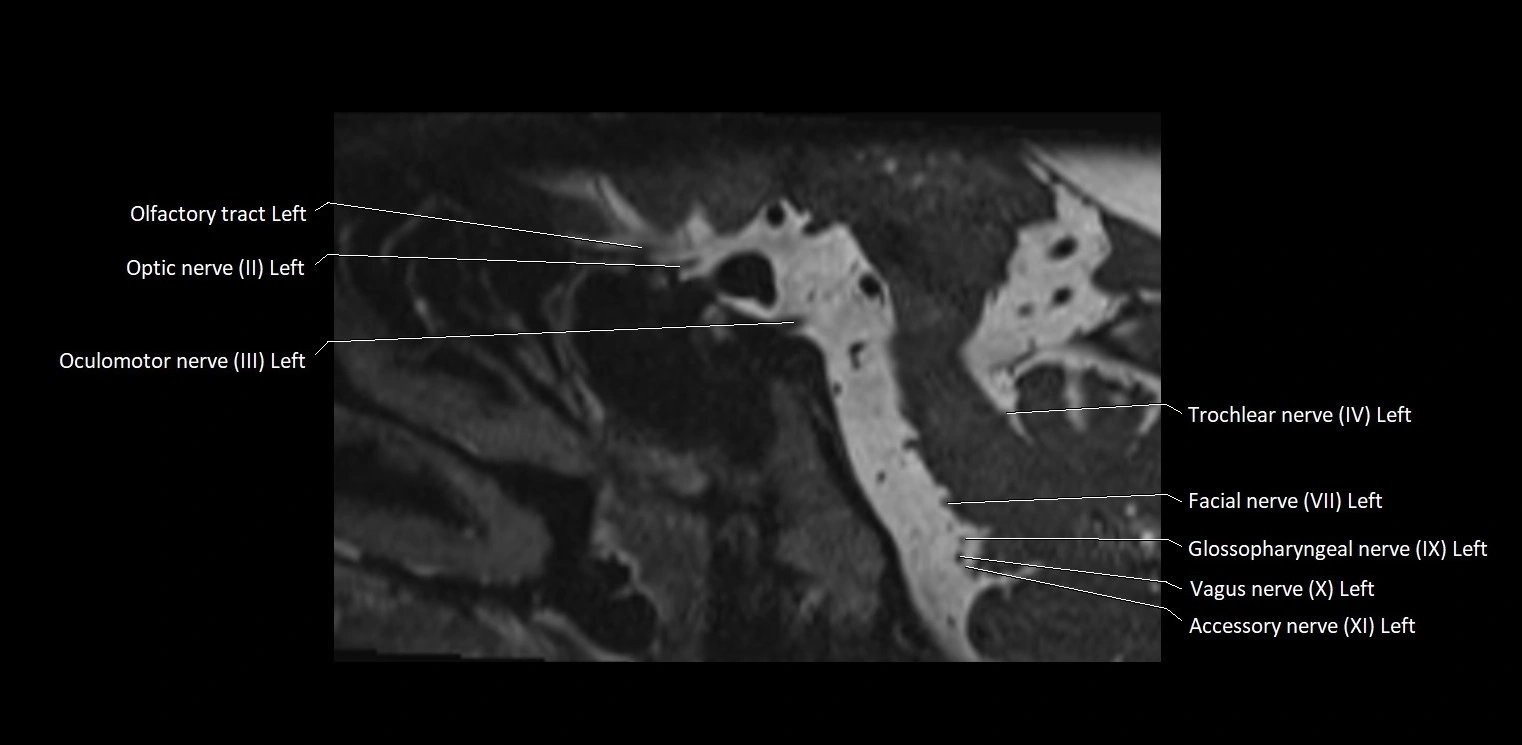

MRI Appearance

• The abducens nerve is a small, thin, linear structure

• Best visualized on high-resolution T2-weighted 3D MRI sequences (e.g., FIESTA or CISS)

• Seen as a hypointense (dark) line running from the brainstem at the pontomedullary junction, traversing the prepontine cistern, and entering Dorello’s canal under the petrosphenoidal ligament, then into the cavernous sinus, and finally the orbit

• May be challenging to visualize in standard MRI due to its small size

• Pathology may be inferred by absence, displacement, or enhancement of the nerve